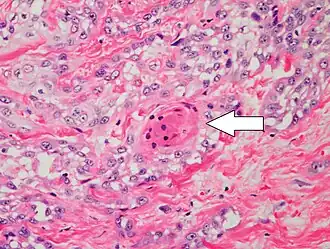

Histological characteristics

Histopathologically, the epidermis in cSCC in situ (Bowen's disease) will show hyperkeratosis and parakeratosis. There will also be marked acanthosis with elongation and thickening of the rete ridges. These changes will overly keratinocytic cells, which are often highly atypical and may have a more unusual appearance than invasive cSCC. The atypia spans the full thickness of the epidermis, with the keratinocytes demonstrating intense mitotic activity, pleomorphism, and greatly enlarged nuclei. They will also show a loss of maturity and polarity, giving the epidermis a disordered or "windblown" appearance.

Two types of multinucleated cells may be seen: the first will present as a multinucleated giant cell, and the second will appear as a dyskeratotic cell engulfed in the cytoplasm of a keratinocyte. Occasionally, cells of the upper epidermis will undergo vacuolization, demonstrating an abundant and strongly eosinophilic cytoplasm. There may be a mild to moderate lymphohistiocytic infiltrate detected in the upper dermis.[12]